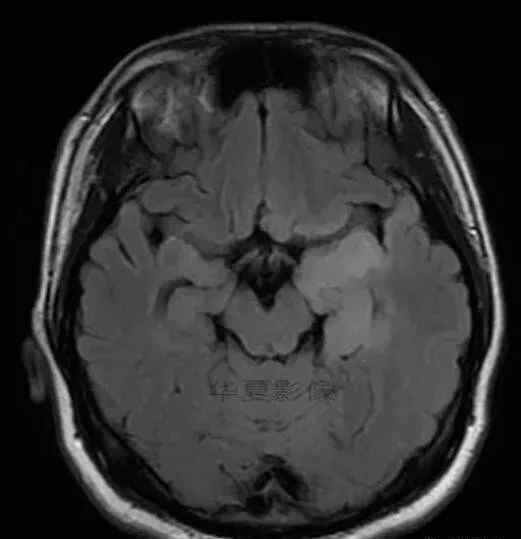

1.左侧颞叶、海马和岛叶T1WI信号低,T2WI信号高

2.病变没有明显的边界

3.占用效果不明显

4.豆状核不受影响